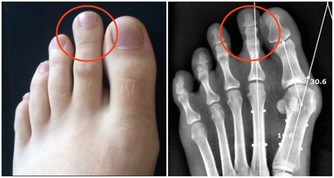

而尿騷味,則通常提示腎有問題了。

人體腎臟具有強大的代償功能,只要腎功能喪失不超過75%,仍能保持人體內環境的穩定。

所以,慢性腎衰病人早期常無明顯臨床症狀,往往容易誤診、漏診,使腎衰病人失去最佳的治療時機。

另外,一些慢性腎衰病人還有一些特殊的臨床表現,如口腔內有氨的氣味,也就是你說的尿味,尿毒症病人更為明顯。

主要原因是,隨著腎功能的減退,腎臟的溶質清除率下降和某些肽類激素的滅活減少,造成多種毒素在血液和組織中蓄積,最常見的毒素就是尿素等。

在口腔中,因為唾液中的尿素被分解為氨,故病人呼出的氣體有尿味。

這種氣味的濃淡隨病情的進退而變化,在病情好轉時,口中尿味淡些,病情加重時尿味變濃。